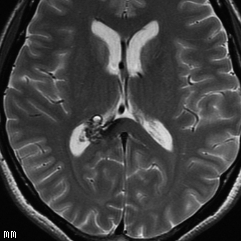

静脈性血管腫(静脈奇形)の合併を見つける方法

左は脳出血のCTです。海綿状血管腫からの出血を疑ったので造影のMRI(右の写真)をしました。血腫の周りに細い線がたくさん見えます。これが静脈奇形(静脈性血管腫)です。脳血管撮影DSAをしなくてもこの合併はわかるのです。この静脈奇形を手術で傷つけるとかなり広い範囲で脳梗塞がおきる可能性があります。